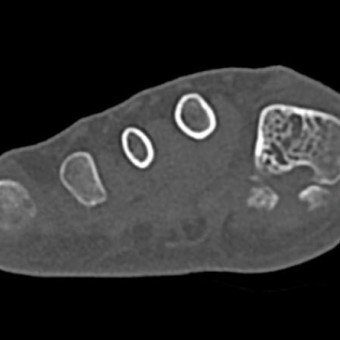

Zur genaueren Untersuchung und Darstellung machten wir daher ein CT, das die Knochen besser darstellt.

Plantarer Osteophyt

3D-Darstellung des Fusses mit Überbein